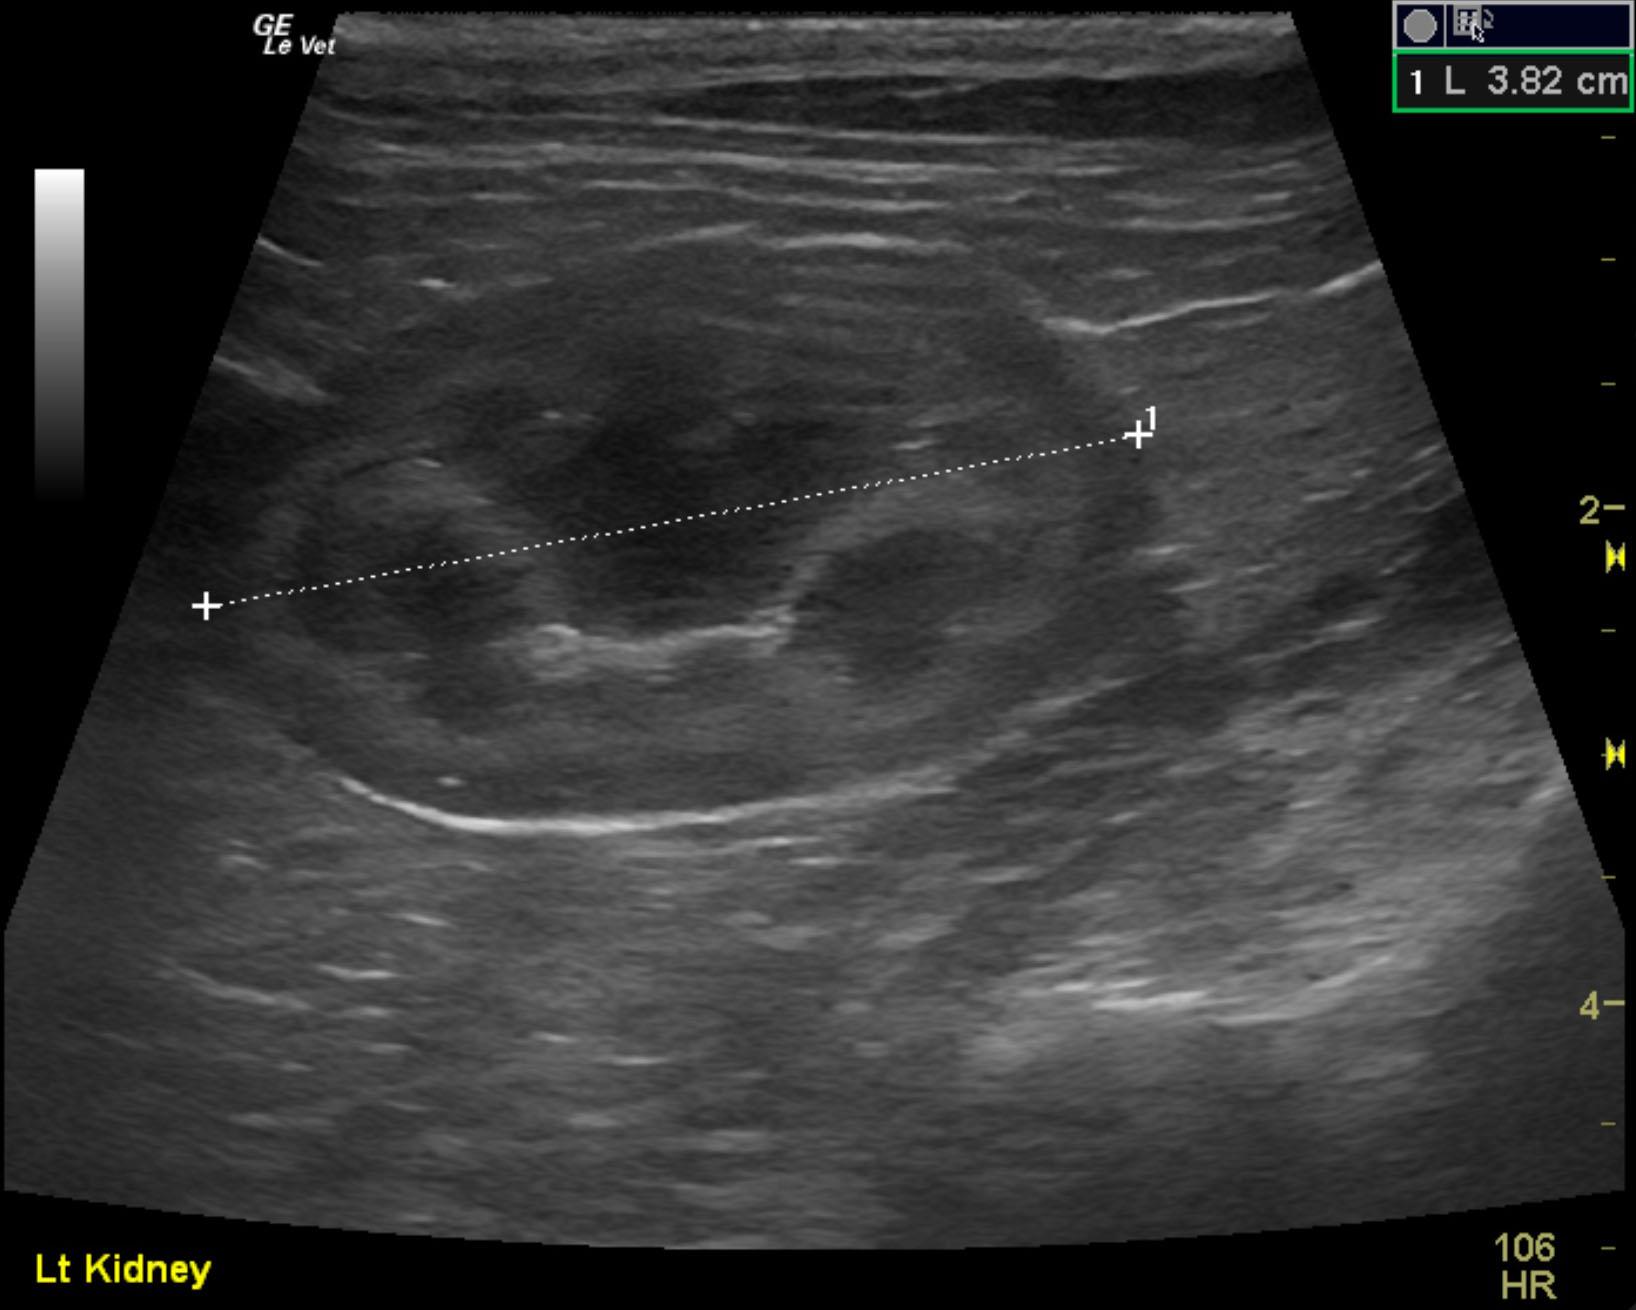

A 2-year-old neutered male DMH cat was presented for urethral obstruction and a possible mass dorsal to the urinary bladder. The cat also had a 5-day duration of diarrhea.